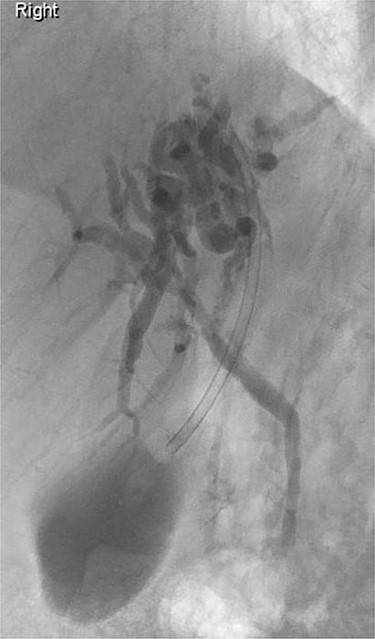

ERCP: cannulation via the major papilla orifice into the CBD draining the right IHDs. There was no communication between the ACBD and the right IHDs.

ERCP: cannulation via the pre-pyloric fistula opening. Contrast outlining the ACBD and the left IHDs.